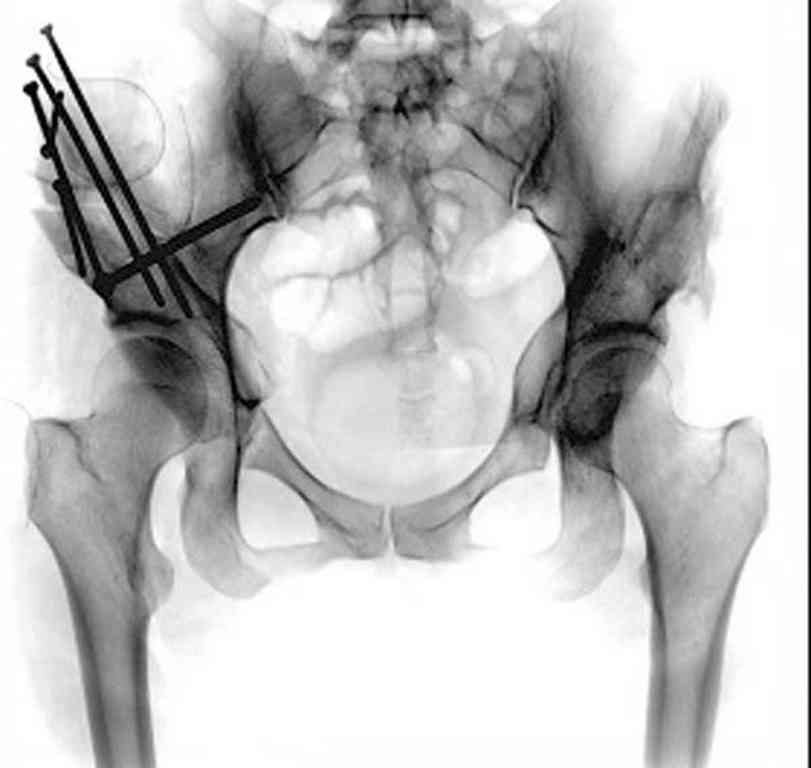

Вложение не в текстовом формате было извлечено…

Имя     : Displasia.jpg

Тип     : image/jpeg

Размер  : 30592 байтов

Описание: отсутствует

Url     : http://weborto.net:8080/pipermail/ortho/attachments/20101217/2fe082a4/attachment-0005.jpg

При более сохранном суставе от дальнейшего разрушения можно было бы сохранить только периориентацией нагрузки на сустав - Периацетабулярной Остеотомией .

После участия в последней конференции "Вреденовские Чтения" в Ст. Петербурге, по представленным докладам, я убедился, что в территории СНГ очень мало специалистов энтузиастов, кто серьезно занимается патологией дисплазии. В большинстве те, кто занимается данной патологией, делают давно забытую тройную остеотомию таза, и доложенные результаты находятся далеко от идеала...

Только коллеги из Вреденовского Института начали работу по тематике сохранения тазобедренного сустава, остеотомия как альтернатива замене сустава. Надеюсь, что скоро в России многие последуют примеру Ст. Петербурга, и тогда уменьшатся цифры по протезированию у молодых.